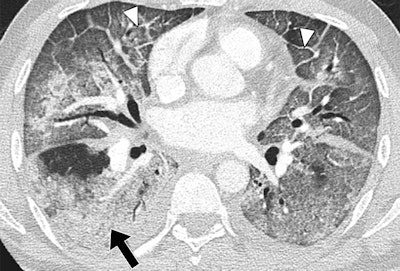

Patients hospitalized with MERS most commonly showed bilateral predominantly subpleural and basilar airspace changes, with extensive ground-glass opacities and less consolidation, concluded the study team from King Abdulaziz University Hospital in Jeddah. The subpleural and peribronchovascular nature of most of the abnormalities is suggestive of an organizing pneumonia pattern, they wrote.

The images showed that airspace opacities were more common than interstitial changes, according to the authors. Five patients had both ground-glass opacities and consolidation -- with ground-glass opacities being more extensive in all but one of those patients. One patient had only ground-glass opacities and another had isolated consolidation.

The radiologists found smooth septal thickening in three of the seven patients, and minimal peripheral reticulation, traction bronchiectasis, and perilobular opacities were found in just one patient. None of the patients had tree-in-bud pattern, cavitation, or intrathoracic lymph-node enlargement, the authors wrote.

The most common CT finding in hospitalized patients with MERS is bilateral predominantly subpleural and basilar airspace changes, with more extensive ground-glass opacities than consolidation, Ajlan and colleagues concluded.

"The predilection of the abnormalities to the subpleural and peribronchovascular regions is suggestive of an organizing pneumonia pattern," they wrote. "Recognizing this pattern in acutely ill patients living in or traveling from endemic areas may help in the early diagnosis of MERS-CoV infection."